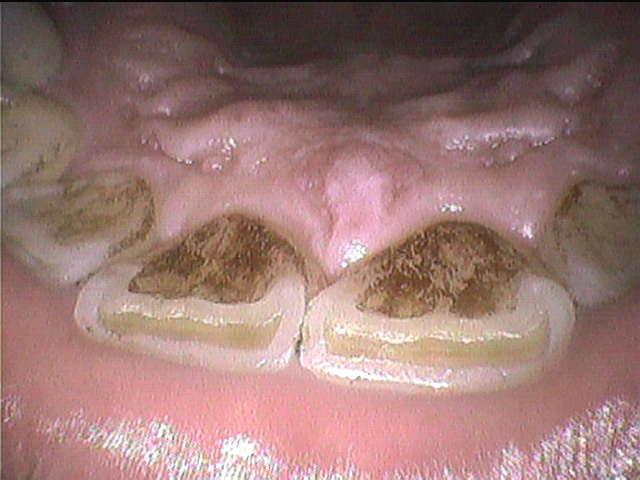

クリーニング前

後

タバコのヤニは、煙に含まれるタールが歯の表面に沈着してしまったものです。

歯磨き粉では、ポリエチレングリコール(PEG)やポリビニルピロリドン(PVP)という成分が

ヤニを溶解する効果があるのでおすすめです。

それでも取れないヤニは、セルフケアで除去するのは難しいため

歯科医院でクリーニングをしましょう。